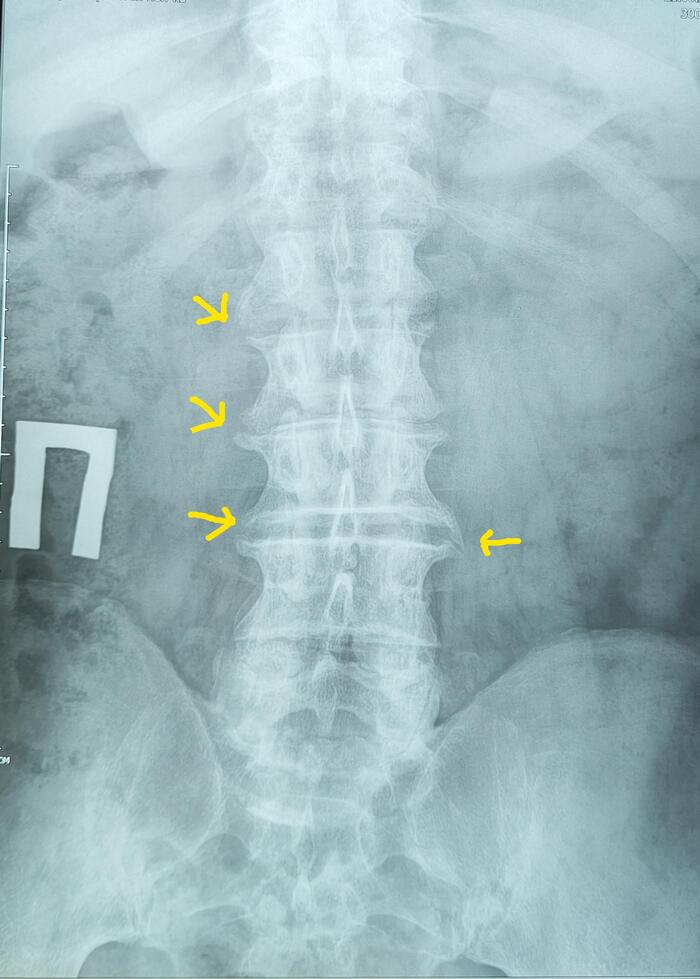

На Р-граммах грудного, поясничного отделов позвоночника определяется S -образное искривление оси позвоночника, с левосторонней дугой, вершиной на Th10,угол девиации 20 град., правосторонней дугой, вершиной на L2, углом девиации 15 град.

Итоговый диагноз: Патологический гиперкифоз грудного отдела позвоночника 4 ст. по Коббу. Клиновидная деформация тел Th6, Th7, Th8 позвонков, как следствие перенесенной остеохондропатии, соответствует болезни Шейермана-Мау.S-образный сколиоз 2ст.Остеохондроз грудного, поясничного отделов позвоночника.